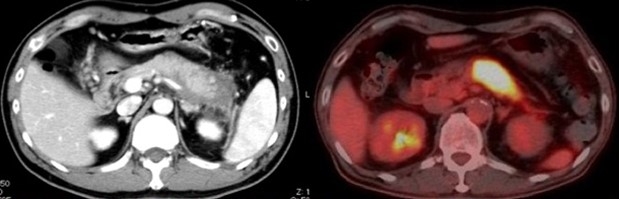

まず、マウスにpoly(I:C)※8を反復投与し、自己免疫性膵炎モデルマウスを作成しました。モデルマウスを用いて検証を行った結果、発症初期には膵臓に炎症の原因とされる形質細胞様樹状細胞はほとんど存在せず、活性化された通常型樹状細胞がサイトカインであるI型IFNとケモカインであるCXCL9・CXCL10※9を産生し、初期の炎症を誘導することが明らかになりました。次に、CXCL9・CXCL10に反応してCXCR3陽性CD4T細胞が膵臓に誘導され、この細胞がさらなる炎症をもたらすことがわかりました。また、CXCR3陽性CD4T細胞はインターフェロン-γ※10を産生し、膵臓にダメージを与える一方で、ケモカインCCL25※11を膵臓で産生します。このCCL25が、最も炎症に大きな影響を与える形質細胞様樹状細胞を最終的に膵臓に引き寄せ、炎症が完成することが明らかになりました。つまり、通常型樹状細胞とCXCR3陽性CD4T細胞が初期の炎症を誘導し、CXCR3陽性CD4T細胞と形質細胞用樹状細胞が炎症を完成させることがわかりました(図)。さらに、完成期には形質細胞様樹状細胞とCXCR3陽性CD4T細胞が相互に活性化しあい、大量のI型IFN・CXCL9・CXCL10・CCL25が放出され、炎症が加速することも突き止めました。また、実際にTLR3・CXCR3・CCL25・I型IFNを阻害すると、炎症はほとんど起こりませんでした。ここから、通常型樹状細胞・形質細胞様樹状細胞・CXCR3陽性CD4T細胞を自己免疫性膵炎・IgG4関連疾患の病的細胞と同定し、病気の初期・完成期におけるこれらの細胞の役割をサイトカイン・ケモカインのレベルで明確にすることができました。

最後に、自己免疫性膵炎・IgG4関連疾患患者の血液を用いた検討を行いました。その結果、活動期の自己免疫性膵炎・IgG4関連疾患では、血液中のI型IFN・CXCL9・CXCL10・CCL25が、健常人・慢性膵炎患者と比較して著明に上昇することがわかりました。また、ステロイドにより病気が改善すると、血液中のI型IFN・CXCL9・CXCL10・CCL25は著明に低下しました。